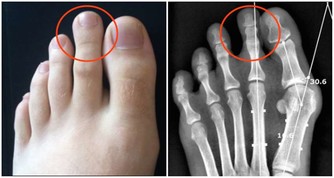

體重適宜肥胖的最大危害是它會帶來許多老年性疾病,容易發生高血壓、冠心病、痛風、膽石症和胰腺炎等病。

此外,老年人體重超重還會增加脊柱和關節的負擔;容易發生背痛、關節炎和關節變形等,

所以老年人要避免老來“發福”,最理想的辦法是控制飲食和體育鍛煉。